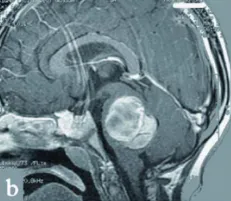

患儿妮娜在经历急性出血和神经功能恶化1个月后,接受脑干海绵状血管瘤手术治疗。临床表现为嗜睡、头痛、右侧偏瘫(伴面瘫)及言语障碍,年幼生命遭受严重打击。病情突然加重的原因系先前确诊的桥脑海绵状血管瘤体积增大、出血,并伴有轻度脑积水。

复查MRI显示:左侧桥脑存在最大尺寸4×3.5×3cm的巨大海绵状血管瘤(图1 a-c)。

术后患儿神经症状持续改善。术后10天MRI检查证实海绵状血管瘤完全切除,显示先前严重增大的脑干已获减压(图1 d)。患儿出院后接受进一步神经功能康复治疗。

图d 术后:显示海绵状血管瘤完全切除,第四脑室大小恢复,脑干压迫解除。